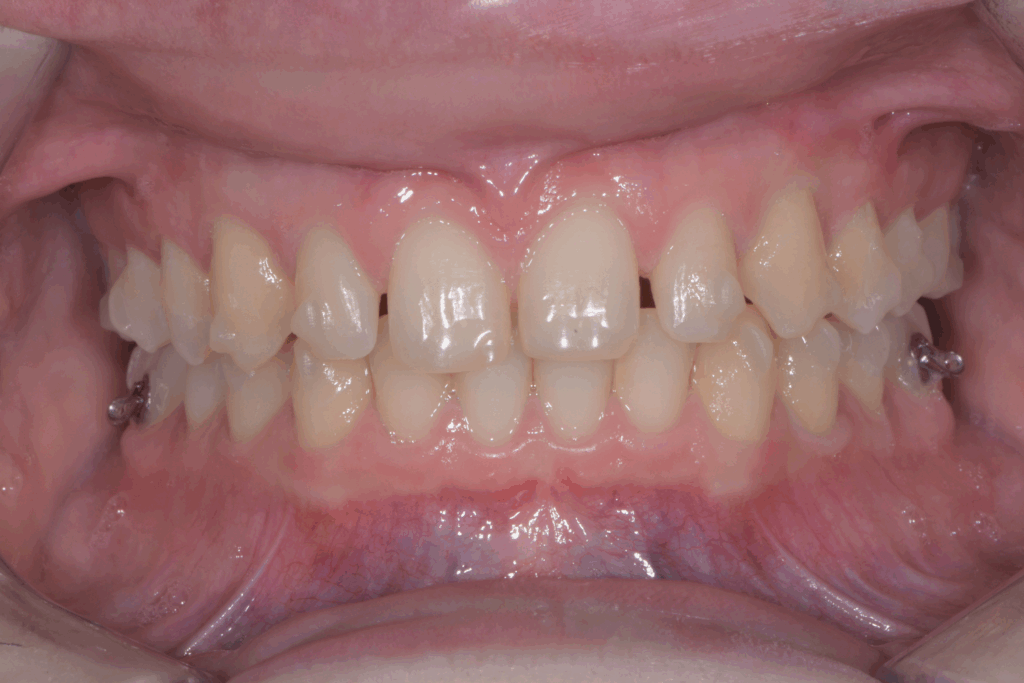

Per affrontare le sfide del caso, abbiamo optato per l’utilizzo di allineatori trasparenti. Questo tipo di trattamento è stato scelto per la sua efficacia nel muovere i denti in modo preciso e graduale, ma anche per la sua discrezione, fondamentale per una paziente in età scolare. Il piano di trattamento ha previsto una serie di allineatori personalizzati, che la paziente doveva sostituire con il passare delle settimane.

Gli obiettivi del trattamento con allineatori erano tre:

- Chiusura degli spazi: gli allineatori sono stati programmati per spostare i denti posteriori e chiudere gli spazi vuoti lasciati dall’agenesia dei settimi, evitando la necessità di impianti o ponti.

- Correzione della verticalità: il trattamento ha lavorato per estrusione e intrusione selettiva di alcuni denti, al fine di correggere il morso profondo e ristabilire una corretta occlusione.

- Preparazione estetica: una volta raggiunta la corretta posizione dei denti, il trattamento ha preparato lo spazio e l’allineamento ideali per la fase successiva.